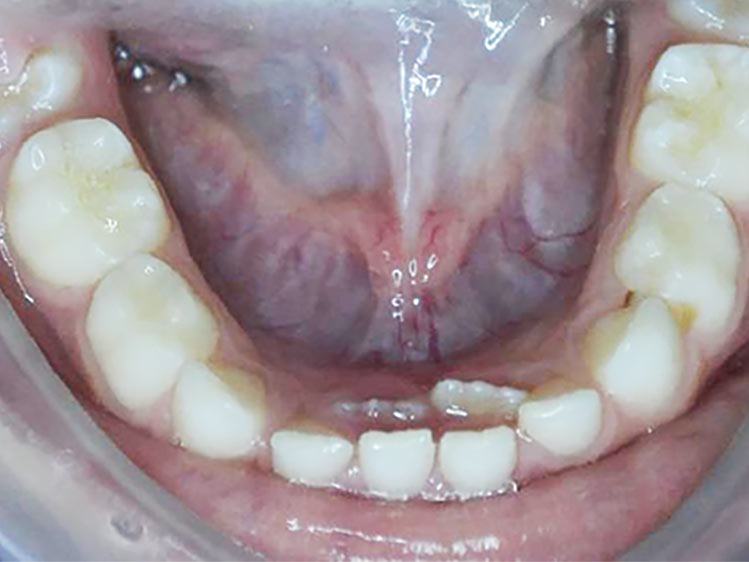

É necessário fazer uma avaliação clínica e radiográfica criteriosa da oclusão do paciente.

Nesse momento tão dinâmico da vida dos pequenos é importante acompanhar de perto as transformações, se certificando se estas mudanças estão acontecendo de forma correta.

Se algo estiver fora da normalidade, o problema poderá ser interceptado e corrigido prontamente, evitando longos tratamentos ortodônticos no futuro.

As chances de correção de uma má oclusão é infinitamente maior quando é possível contar com o crescimento e desenvolvimento da criança.